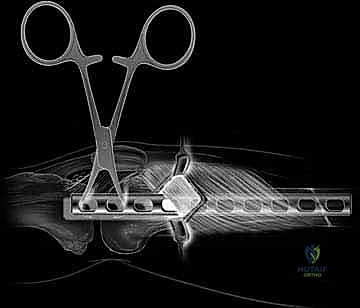

Navigating the lateral thigh requires a deep understanding of its fascial and muscular layers to exploit the correct avascular planes. The outermost boundary is the tensor fascia lata (TFL) and its distal continuation, the iliotibial (IT) band. This thick, fibrous structure must be incised to access the deeper muscular compartments. Beneath the IT band lies the vastus lateralis, the largest and most powerful muscle of the quadriceps femoris group. The vastus lateralis originates from the greater trochanter and the lateral lip of the linea aspera, wrapping around the lateral aspect of the femur.

The critical maneuver in submuscular plating is identifying the interval deep to the vastus lateralis. Specifically, the surgeon must dissect beneath the obliquely oriented distal fibers of the vastus lateralis to access the lateral femoral periosteum. This epi-periosteal plane is remarkably avascular and can be developed with minimal blunt dissection. By tunneling the plate within this specific plane, the surgeon lifts the vastus lateralis off the femur without stripping the periosteum or disrupting the muscular perforators that supply the bone.

Step-by-Step Surgical Approach and Fixation Technique

Clinical & Radiographic Imaging Archive